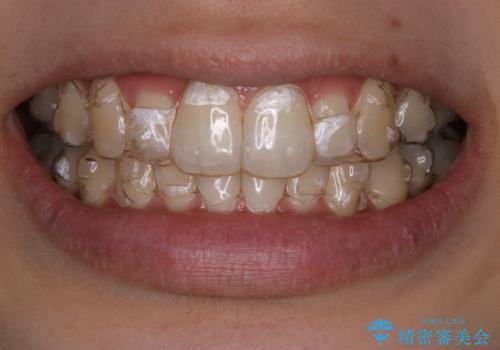

インビザラインでのマウスピース矯正中にPMTCでステインの除去

- インビザラインでの矯正治療中に着色を取るクリーニンングも行いたいとのことでした。PMTC30分コースを行いました。

インビザライン矯正治療はマウスピースを長時間使用するため、歯石や汚れ・着色などが付着したままだと、フィットが悪くなったり、口臭が強く出たりする原因につながることもあります。